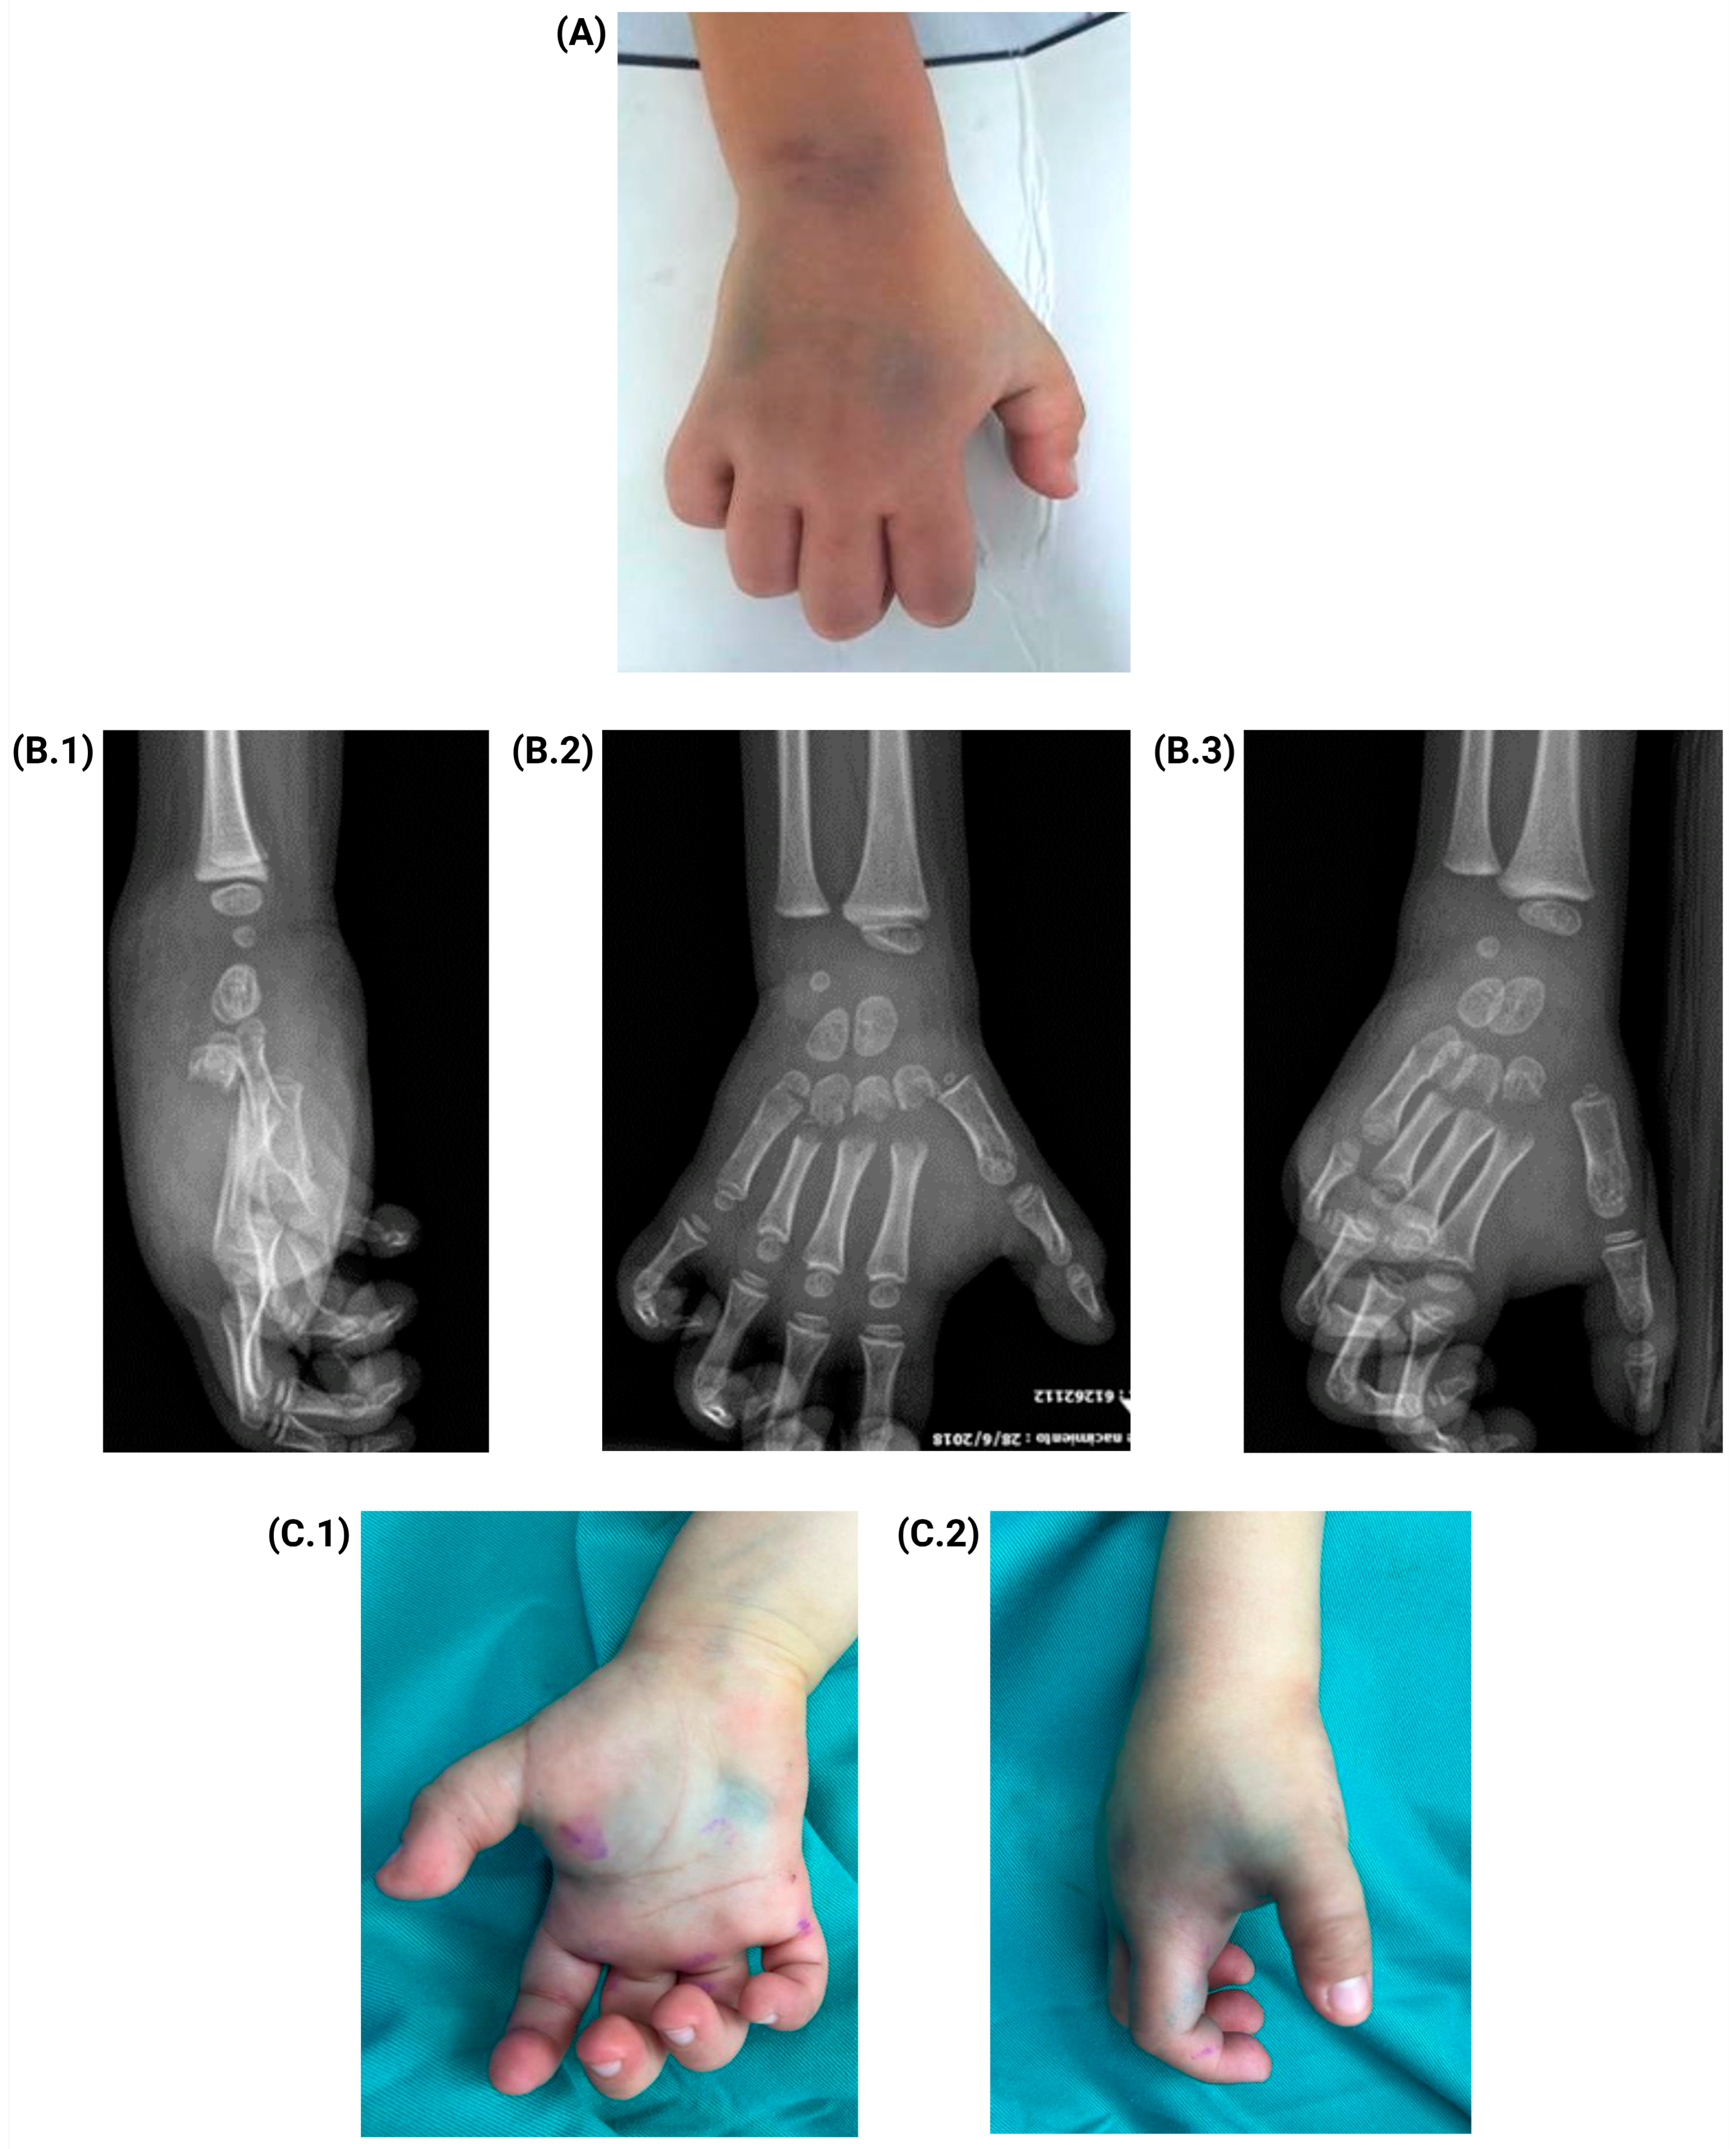

Acute Compartment Syndrome with Multiple Metacarpal Fractures in the Hand of a 5-Year-Old Boy: A Case Report of Successful Resolution with Delayed Primary Closure

2. Case Presentation